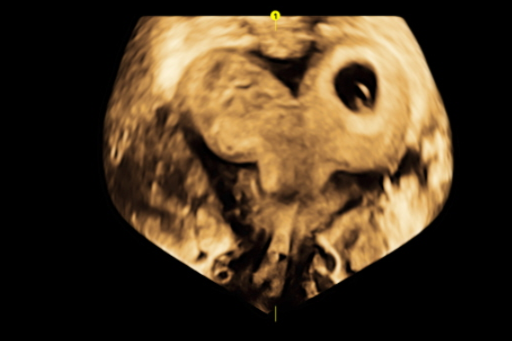

「从影像检查结果看,这位患者的胃部肿瘤直径约 15 cm,肿瘤较大,而且位于胃底部,侵犯了腹段食管,如果手术时切除腹段食管较多,无法进行食管肠道吻合,还需要做好开胸手术的准备,向上端食管进行缝合。」树兰(杭州)医院胃肠外科吴芳医师介绍。

经过详细的术前评估与研判,手术当天,当叶再元教授主刀打开腹腔,看到巨大肿瘤时,还是让手术室的医护人员大吃一惊,「整个胃都被肿瘤占据了,而且已经溃烂破败,有的地方还淌着黑水,散发出一阵阵恶臭味。」作为手术助手,吴芳表示,巨大肿瘤导致手术视野非常差,而且胃内最大的血管——胃左动脉被肿瘤严密包裹,几乎找不出手术空间。